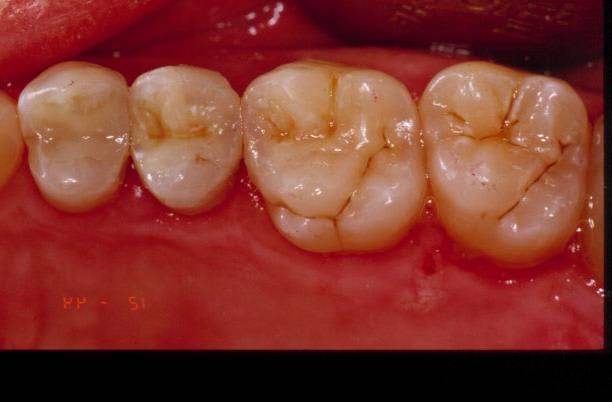

Je ne vois pas à part un petit sillon en vestibulaire où l'onlay est mal ajusté ?

Maintenant pour l'esthétique je suis bien d'accord que c'est pas le top mais ce n'était pas le but recherché (bien que la patiente trouve cela parfait), je voulais avant tout préserver la pulpe et rappelons qu'à une distance classique le regard n'est pas attiré (on ne se regarde pas toute la journée au téléobjectif).

Tiens Dudule , ce que moi je vois comme défauts d'adaptation.

Les bactéries pour la récidive n'ont pas de téléobjectif !!!!!

En vestibulaire ok, je l'ai même dit au départ... pour le reste je suis absolument pas d'accord (surtout en lingual où l'adaptation est top). Je n'ai par contre pas poli le joint après avoir retiré les excès (quelle infamie...).

C'est sur que le superbond étant translucide, on voit une différence de teinte au niveau du joint plus importante qu'avec des collages dual.

Comment peut-on juger de l'ajustage de la restauration sur une photo comme çà, restons sérieux.

lui mm trouve le joint vestibulaire mediocre, je trouve le resultat esthetique mediocre.

l esthetique aurait été ameliorée en englobant les cuspides, ça evitait le raccord au flow qui fait qd mm desordre ( qu'est ce qui se passe si ton flow se barre? donc toute ta reconstruction ceram top level depend d'un flow qui est qd mm pas le materiau qui vieillit le mieux et dont l'etancheité est rassurante ) ça eliminait les risque de fractures.

Premièrement je n'ai jamais dit que c'était mon premier onaly, juste que j'en avais pas fait à la fac. Deuxièmement, ça fait 10 minutes que je fais joujou avec mon ordi (constraste luminosité), tu dois avoir des yeux bionic car je ne voyais rien en bouche et je ne vois toujours pas où il y a un défaut d'étanchéité à part le sillon entre les 2 cuspides vest et l'onlay... mais bon je dois être très très mauvais. Troisièmement mon choix qui n'était peut-être pas le plus judicieux de ne pas toucher ces fameuses cuspides vestibulaires vient du fait que j'avais peur de rendre une dent symptomatique alors qu'elle ne l'était absolument pas malgré la carie pré-op et d'autre part que l'anatomie fait arriver le point de contact de la cuspide antagoniste sur l'onlay et pas sur la dent. Cherchant évidemment à progresser (sinon j'aurai pas posté), pourriez vous me posté des photos de joint avec superbond parceque moi j'ai à chaque fois cet aspect translucide fin à la jonction de mes collages. Ce post aura au moins eu le mérite de permettre un débat et c'était là mon but sur préservation vitalité ou non. (car je continue à ne pas voir où est le mauvais ajustage).